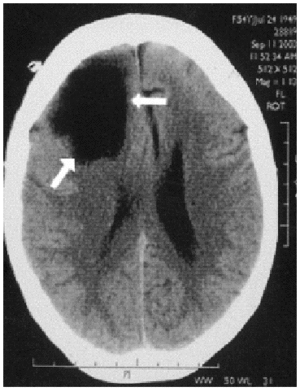

Paciente de 54 años con antecedentes de hipertensión arterial que acude a urgencias por un episodio brusco de caída al suelo, con disartria, desviación de la comisura bucal y de la mirada a la izquierda, vómitos y una crisis tonicoclónica generalizada. Ingresa en la Unidad de Cuidados Intensivos (UCI) con la sospecha de accidente cerebrovascular agudo, con los ojos abiertos, midriasis bilateral, desconexión del medio sin respuesta a estímulos y desviación de la mirada a la izquierda, por lo que se procedió a su intubación y conexión a ventilación mecánica. Se realiza una tomografía computarizada craneal que objetiva quiste aracnoideo gigante con gran efecto expansivo, desviación de la línea media y desviación de tronco. Se efectúa una intervención urgente con drenaje del quiste. La evolución inmediata es buena; al alta de la UCI la paciente se encontraba consciente y orientada, colaboradora y sin focalidad neurológica. Fue derivada a la planta de neurocirugía para la realización de una derivación quiste-peritoneal.